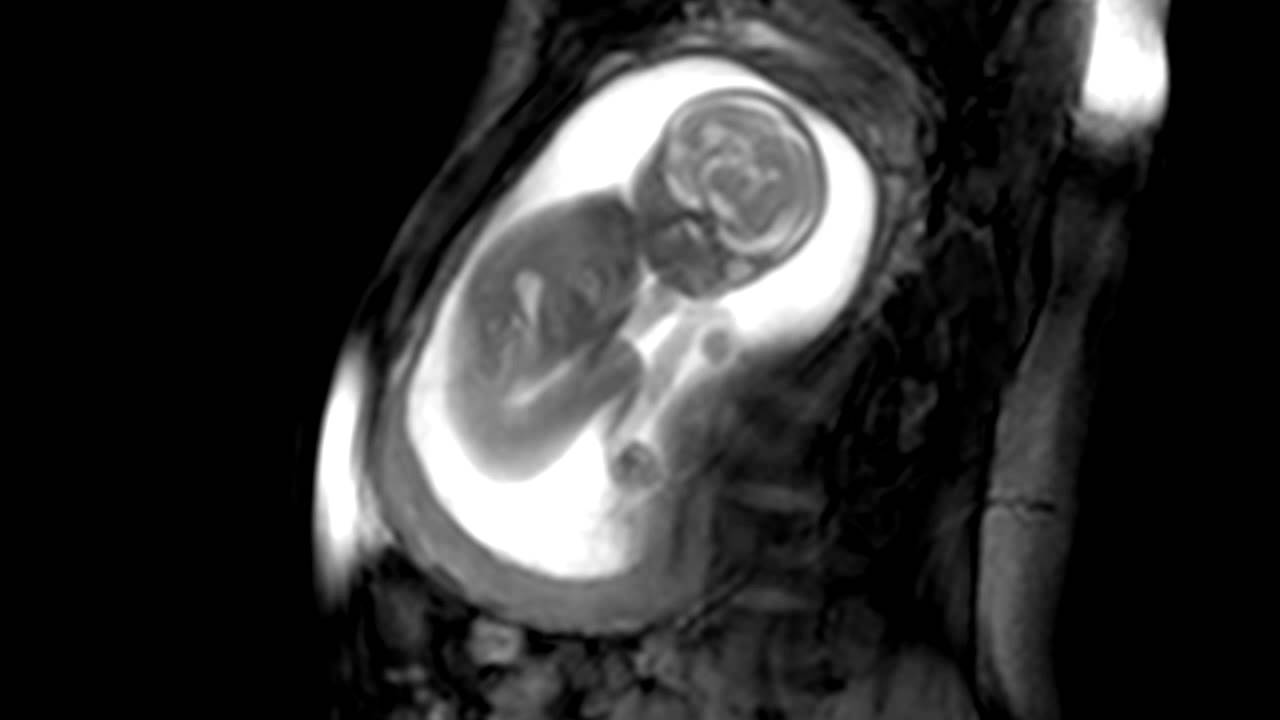

I movimenti fetali visti con la MRI: presto nuove diagnosi più precise (VIDEO)

Redazione Universo Mamma

iFind, il nuovo progetto di ricerca per una migliore e più accurata diagnosi fetale: individuare eventuali anomalie precocemente consente di intervenire prima e meglio.